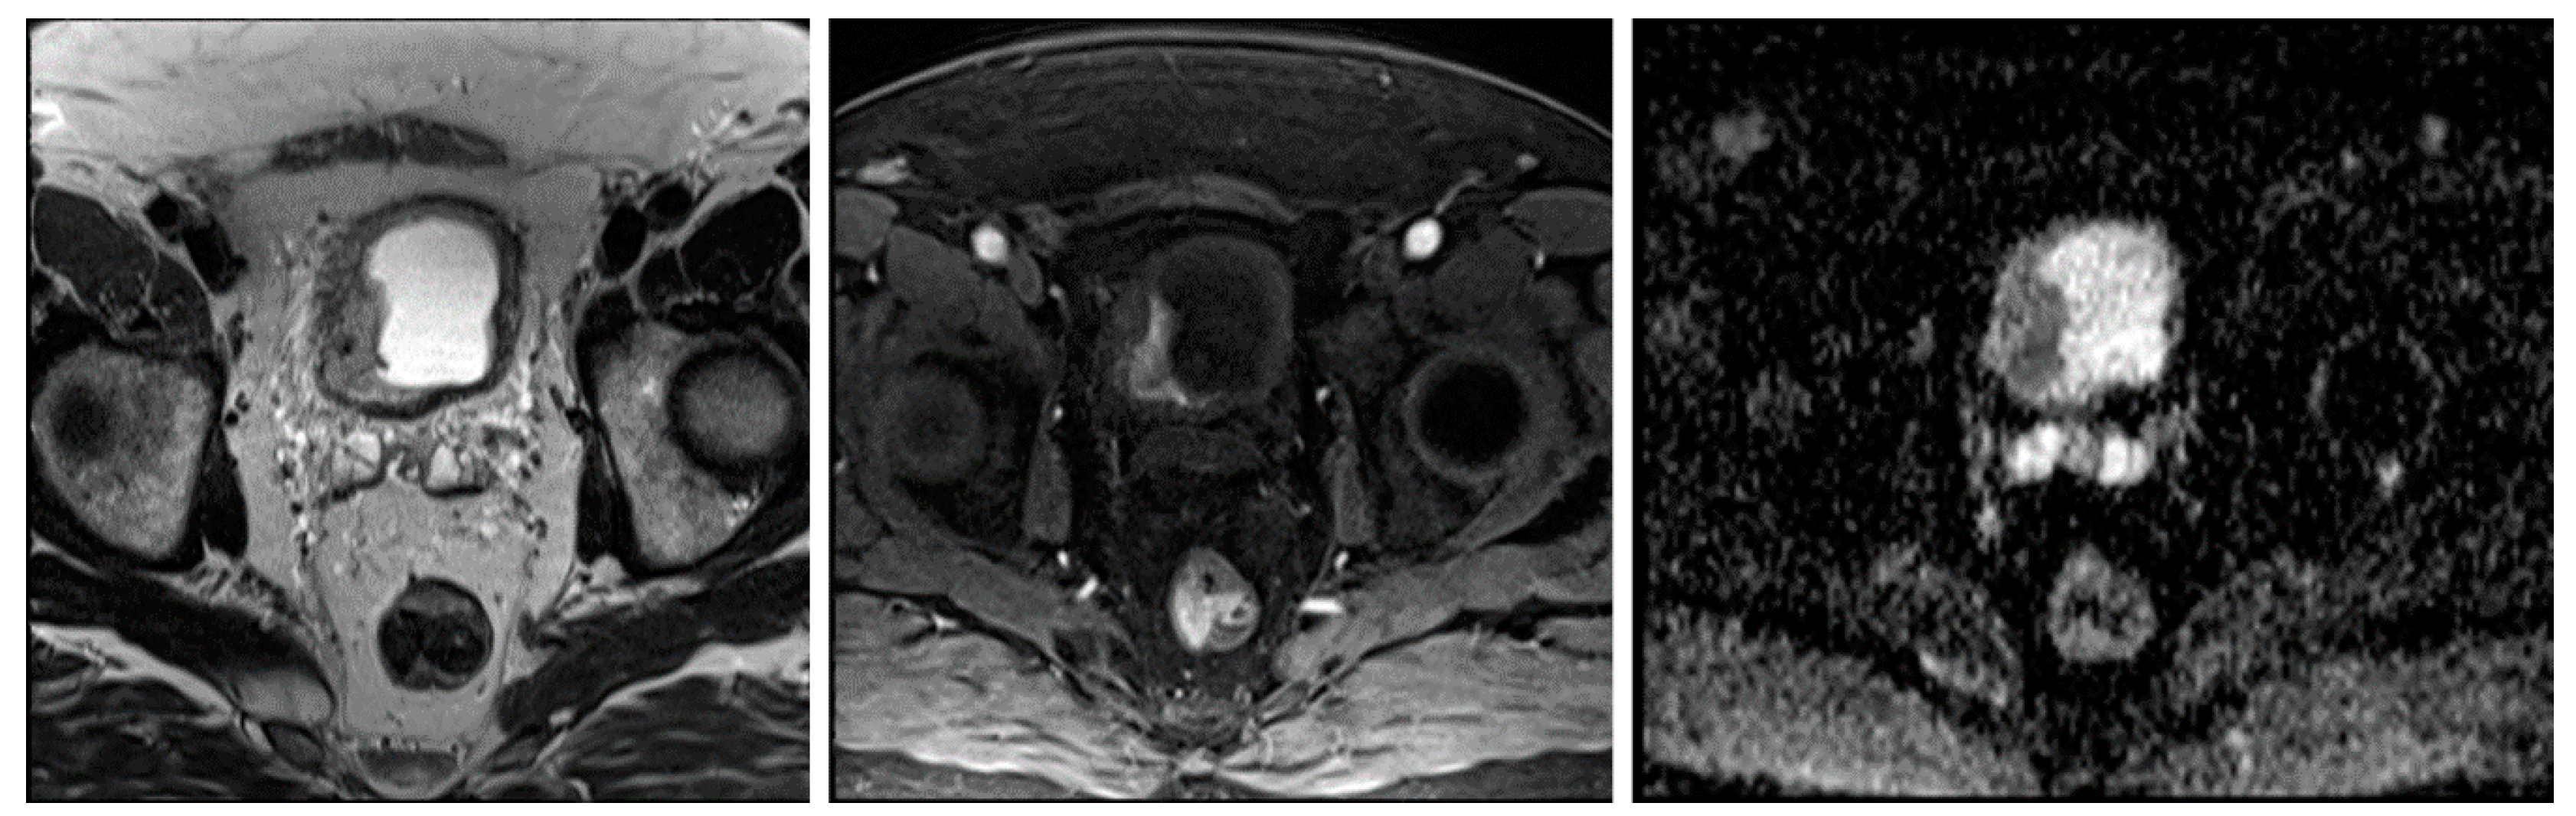

2.2. Magnetic Resonance Imaging

2.3. Image Segmentation